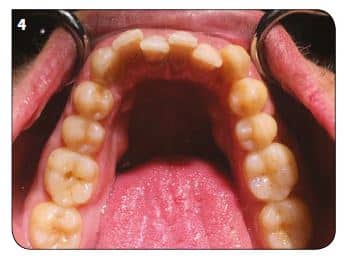

Un patient de 30 ans vient au cabinet pour un encombrement de sa zone antérieure tant maxillaire que mandibulaire. À l’examen clinique, hormis sa DDM, il était en classe 1 molaire des deux côtés, facilitant la prise de décision dans son plan de traitement (Fig.1 à 4).